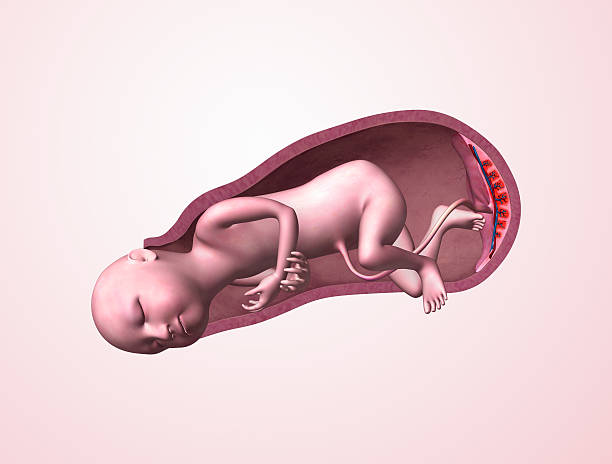

In a 5 days embryo transfer, an embryo in a more advanced stage, called a blastocyst, is formed-a stage where cells have begun to differentiate into inner cell mass and trophectoderm. As per Dr. Aravind’s IVF, transferring the embryos at this stage can improve implantation because only the strongest embryos usually make it to day 5. Also, this natural synchrony with the uterine environment may support the chance of pregnancy. For couples who wanted to improve the chances of success, modern IVF protocols tend to prefer a number of blastocyst transfers.